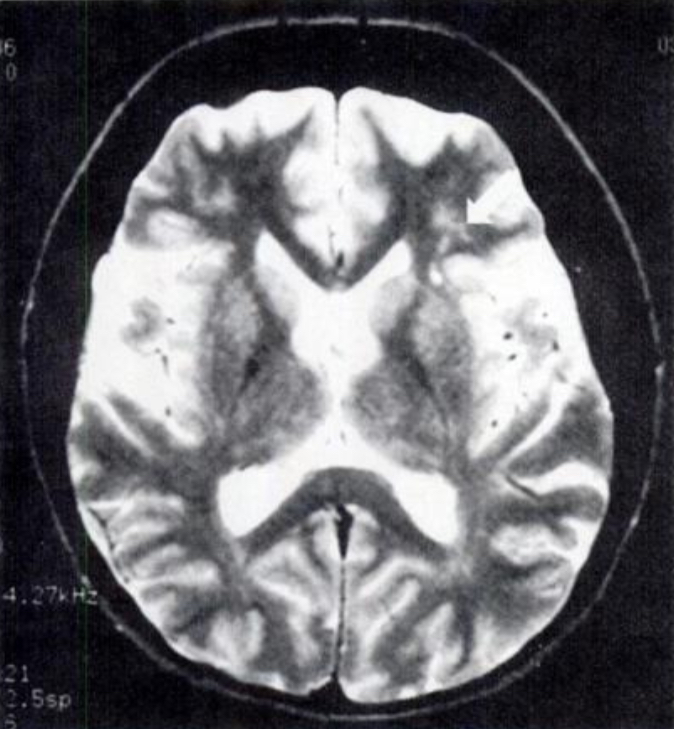

После сеанса гипноза пациентка в течение короткого периода времени помнила события так, как она их описывала; затем она стала крайне возбужденной, бредовой и безутешной. Она отказалась снова входить в транс. Она решительно отрицала, что имело место какое-либо сексуальное домогательство, заявив: "Я бы знала, если бы это произошло". Ее семья не знала о подобном событии, и в настоящее время факт домогательства остается неподтвержденным. Был поставлен предварительный диагноз ПТСР с психотическими признаками и начато комплексное лечение.; Она включала фармакотерапию широкого спектра действия для уменьшения симптомов, еженедельную психотерапию, направленную на выявление и переосмысление травмирующих событий, а также более строгое ведение пациента. Флуоксетин был начат с дозы 10 мг/сут с планируемым максимальным снижением в течение 3-4 месяцев, чтобы свести к минимуму как сексуальную компульсивность, так и расстройства настроения. Однако при приеме 60 мг флуоксетина в день у пациентки наблюдалось значительное снижение сексуальной активности. Она сильно разозлилась и резко прекратила принимать все свои лекарства, что потребовало срочной госпитализации. Меньшая доза, 40 мг/сут, помогла ей справиться с расстройством настроения, но не изменила ее эротических пристрастий и постоянной мастурбации. Кроме того, для блокирования ее гиперактивности и симпатической реакции был использован бета-блокатор (пропранолол по 10 мг три раза в день). Поскольку в прошлом у нее не было реакции на обычные нейролептики, было начато лечение атипичным нейролептиком (рисперидон, 3-6 мг/сут). При приеме рисперидона в дозе 3 мг/сут у пациента наблюдались экстрапирамидные побочные эффекты, и он отказался увеличивать дозу. В течение первых нескольких месяцев пациентка прекратила принимать все свои лекарства, потому что "они не работают". В попытке стабилизировать настроение были проведены краткие тесты на карбонат лития и вальпроевую кислоту, но пациентка отказалась продолжать прием каких-либо препаратов. Из-за трудностей с соблюдением режима клозапин не назначался. В течение 10 месяцев пациентка постепенно становилась менее тревожной, более уверенной в себе и интерактивной. Ее бредовая система не изменилась, и, хотя ночные кошмары и приступы бессонницы продолжались, она смогла отвлечься на повседневные дела. Она предприняла несколько безуспешных попыток заняться работой и учебой, но жаловалась на дневную сонливость и трудности с концентрацией внимания на сложных задачах. Была получена консультация для оценки возможной нарколепсии. Дневная сонливость пациента характеризовалась внезапным появлением галлюцинаций, трудностями при пробуждении, спутанностью сознания и дезориентацией с редкой катаплексией, но не была отмечена автоматизмом, как это можно наблюдать при височной эпилепсии. Ночная полисомнограмма (тест на множественную латентность сна) выявила короткую латентность сна в серии из пяти дневных переходов и фазу быстрого сна в трех из пяти. Был диагностирован синдром нарколепсии-катаплексии, и пациентка начала принимать кломипрамин по 50 мг два раза в день. Первоначально она сообщала об улучшении ночного сна, в том числе о значительном уменьшении числа ночных кошмаров; однако при дополнительном психосоциальном стрессе у нее наблюдалось обострение симптомов. Из-за неполного ответа пациента на лечение ПТСР и связи нарколепсии с повреждением ЦНС (например, инфекцией), возможность болезни Лайма как этиологии была пересмотрена, несмотря на первоначальные неубедительные титры антител. Была получена магнитно-резонансная томография (МРТ) головного мозга с контрастированием гадолинием, которая показала рассеянные точечные очаги аномалий сигнала диаметром 1-2 мм в подкорковом белом веществе на Т2-взвешенных изображениях, преимущественно в лобных долях (рис. 1).

Не было отмечено увеличения желудочков или аномального увеличения паренхимы или лептоменингеальной области. Для определения функционального мозгового кровотока была проведена однофотонная эмиссионная компьютерная томография (ОФЭКТ), в то время как пациент активно галлюцинировал. Это выявило более низкий, чем обычно, кровоток в лобно-височных областях с обеих сторон (рис. 2).;

очагов ишемии отмечено не было. Поскольку это состояние может быть связано с облитерирующим процессом в кровеносных сосудах среднего размера, была проведена неврологическая консультация; при отсутствии инфаркта не было показаний к назначению церебральных вазодилататоров или антикоагулянтов. На основании совокупности данных анамнеза о начале заболевания и результатов анализа сыворотки крови, ликвора и МРТ диагноз пациента был изменен на возможный нейроборрелиоз (болезнь Лайма, поражающая центральную нервную систему). Был установлен чрескожный постоянный центральный венозный катетер, и пациентка получила 4-месячный курс ежедневного внутривенного введения цефтриаксона, который вводила бригада по уходу на дому. После 4 недель антибиотикотерапии повторные серологические исследования на вирус Лайма показали более высокие, чем обычно, титры (0,478; отрицательный результат 0,117), а СМЖ выявил наличие антител IgM (39 кДа, 41 кДа и другие); эти данные соответствовали острой боррелиозной инфекции и были достаточными для соответствия критериям CDC для выявления активный нейроборрелиоз. Симптомы пациентки не менялись до четвертого месяца антибактериальной терапии, когда она начала "чувствовать себя лучше". Ее бредовая система, хотя и оставалась неизменной, стала менее навязчивой, и она впервые за 7 лет смогла работать полный рабочий день. К сожалению, пациентка восприняла это новоприобретенное средство как "лекарство" и решила прекратить внутривенную терапию антибиотиками. Три недели спустя у нее началось полномасштабное обострение симптомов, потребовавшее госпитализации. Были проведены консультации с коллегами, которые опубликовали сообщения о случаях длительной антибактериальной терапии рефракционного или рецидивирующего нейроборрелиоза, и было принято решение возобновить внутривенную терапию.